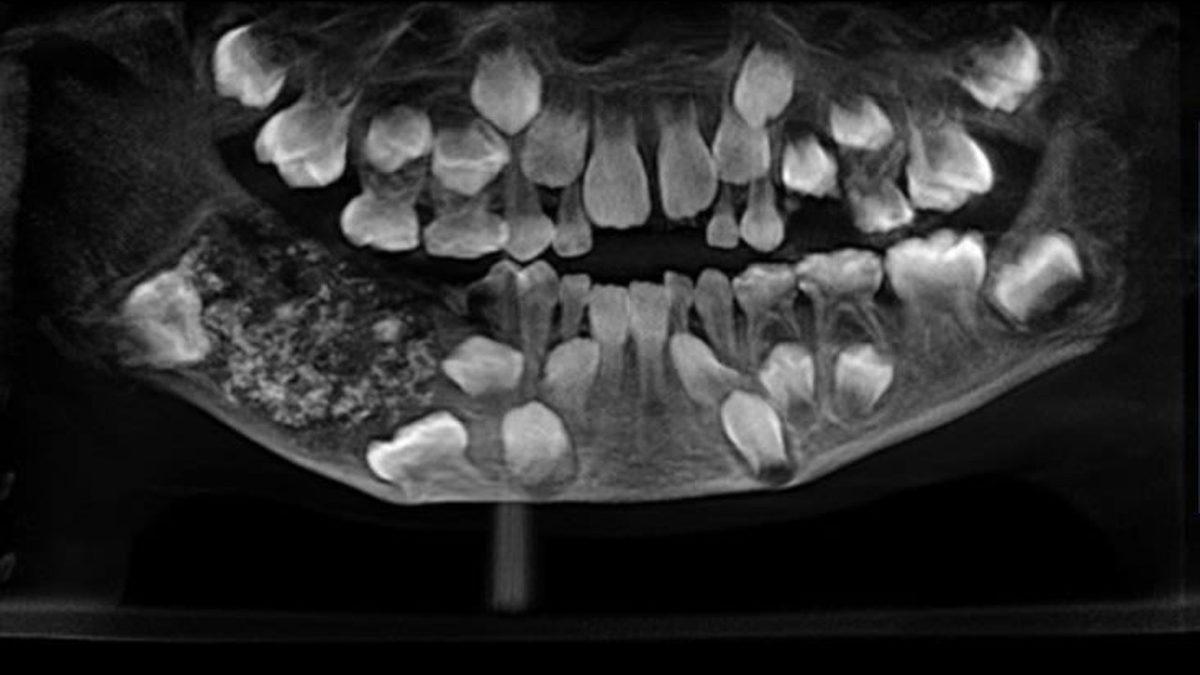

Yani dişler, oluştuğu günden ölüme dek biyolojik olayları kaydediyor. New York Üniversitesi’nden bir araştırma ekibine göre, diş köklerini oluşturan malzeme; hastalıklar, doğum, menopoz gibi vücudun maruz kaldığı streslerin kaydını tutuyor.

Diş köklerini kaplayan sementum isimli bu madde, normal doku oluşumunu etkileyen fizyolojik stres faktörlerine bağlı, gözle görülür ve ayrıca büyüme çizgilerini kaydedebiliyor. Yani ömür boyunca yaşanılan her bir stres, dişlerde yeni çizgiler oluşturuyor.

Araştırmacılar, bu bulgulardan bir kez daha emin olmak için yaşları 25 ila 69 arasında değişen 15 kişinin, toplamda 47 farklı dişini inceliyor.

Ayrıca kişilerin; yaşları, sahip olduğu hastalıklar, hareketlilik durumları ve hayatları boyunca yaşadıkları stresli anlar ve büyük anlar not ediliyor. Sonrasında bu kişilerin diş köklerindeki sementum halkaları, geniş bir görüntüleme tekniği ile inceleniyor.

Dişlerde bulunan bu sementum halkalarının, hangi yaşlara denk geldiği de hesaplanıyor. Sonuç olarak ise ağız içinde rengi farklı olan halkaların, insanların önemli yaşam ve biyolojik olaylar geçirdiği yaşlara karşılık geldiği anlaşılıyor.